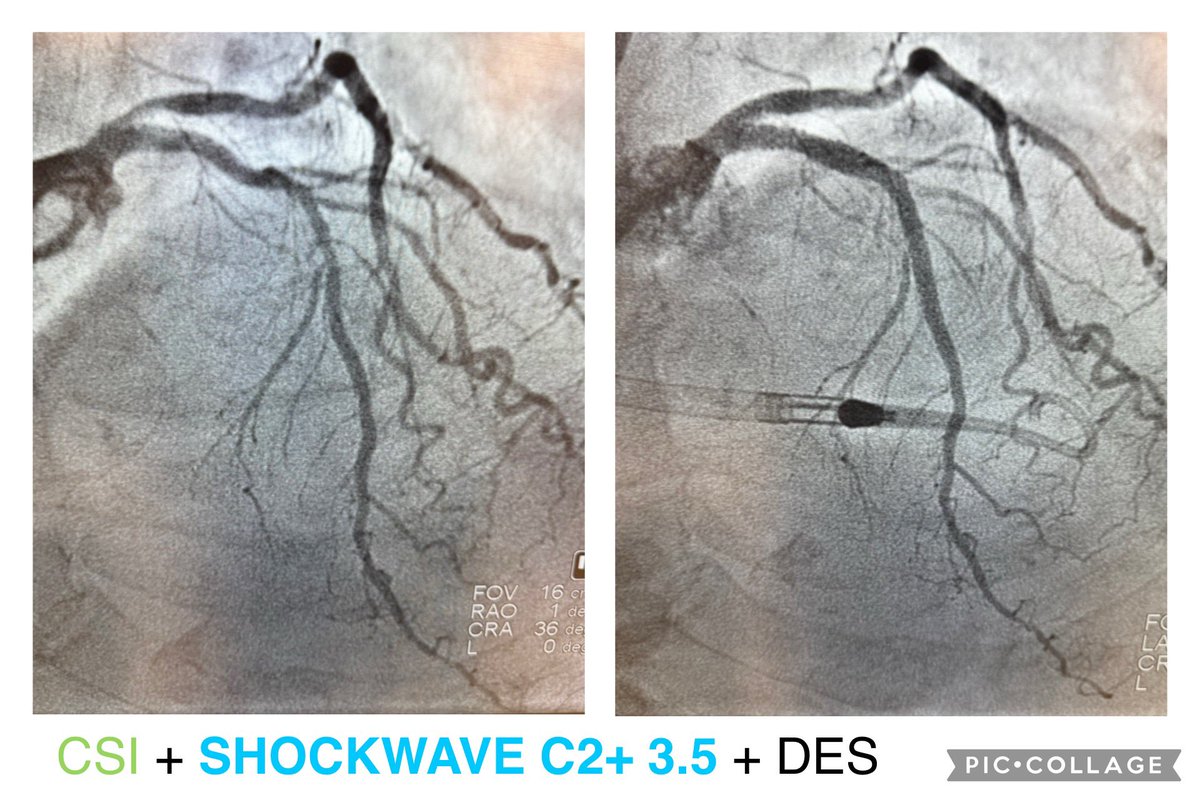

Thursday in the Cath Lab — A Day in Pictures Case 1: High-risk PCI of the left main, LAD, and D1, supported with Impella. Case 2: High-risk PCI of the left main, LAD, and LCx, also supported with Impella.